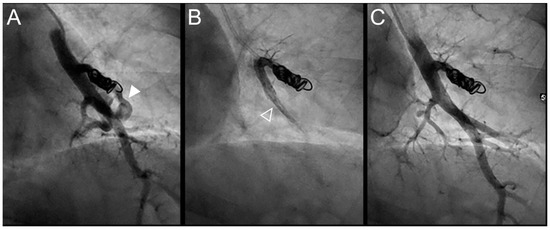

Figure 6.

Case example of a 35-year-old man treated for a recurrent simple pulmonary arteriovenous malformation in the right lower lobe. The pulmonary angiograph showed a distance between the last coil and a healthy arterial branch too short to add additional coils. Embolization was thus performed using Onyx® (0.4 mL) to fill the afferent artery upstream and in the pre-implanted coils, without any leak neither in the aneurysm nor in the vein. It resulted in an immediate complete occlusion until 46 months after the procedure when a recurrence was reported. (A). Opacification of the afferent artery of a PAVM in the lower right lobe showing a recanalization through the pre-implanted coils. (B). Opacity in and upstream (empty arrowheads) the coils showing the distribution of the Onyx®, without any evidence of a leak in the aneurysmal sac, but with a leak in the small arterial branches. (C). Opacification of the afferent artery showing the absence of opacification of the aneurysmal sac and the efferent vein in favor of immediate occlusion. A perfusion defect was identified in a sub-segmental territory (full head arrow), not related to a symptomatic lung infarction.